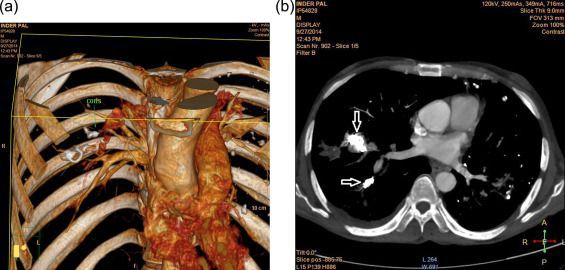

Rasmussen’s aneurysm is a pseudo-aneurysm which develops adjacent to the tuberculous cavity secondary to inflammation and dilatation of branch of pulmonary artery. It is a potentially fatal complication of cavitary tuberculosis. Rasmussen’s aneurysm can cause massive hemoptysis. Reference: https://www.ncbi.nlm.nih.gov/pmc/articles/PMC4681976/ Image via: https://www.sciencedirect.com/science/article/pii/S0019483215002424